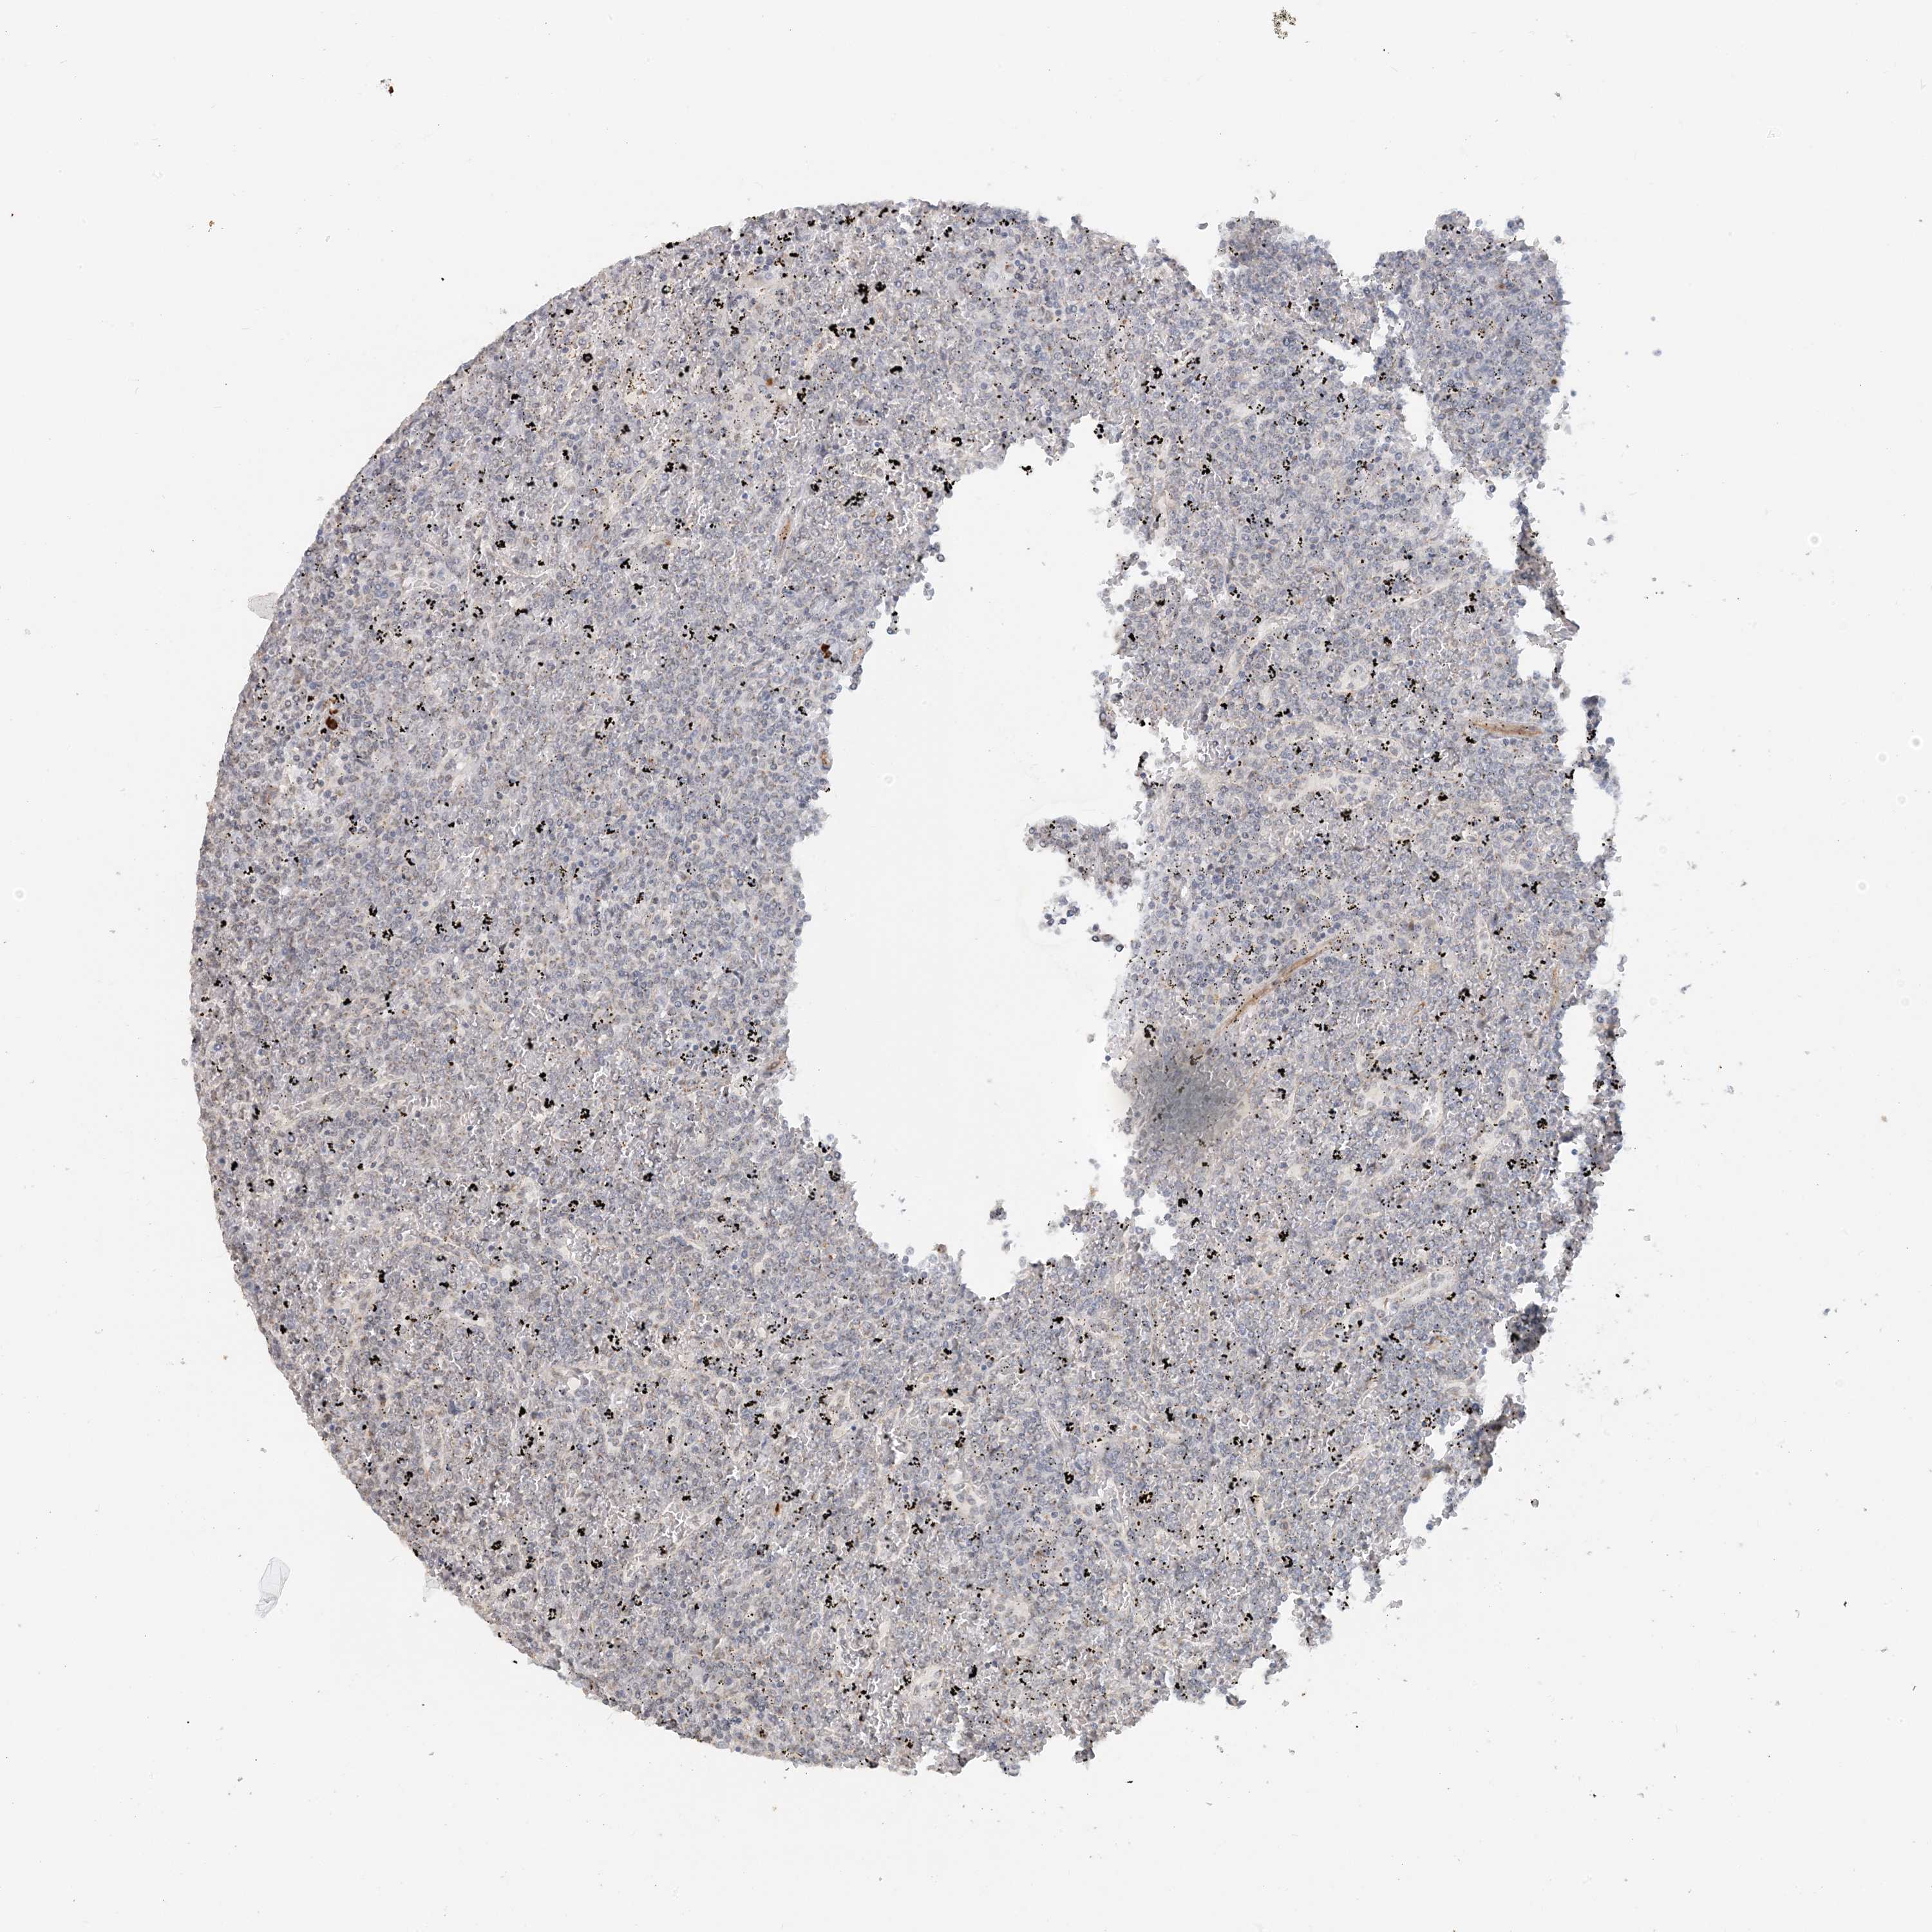

CANCER LYMPHOMA Show tissue menu

LYMPHOMA - Protein expressioni

A mouse-over function shows sample information and annotation data. Click on an image to view it in a full screen mode. Samples can be filtered based on level of antibody staining by selecting one or several of the following categories: high, medium, low and not detected. The assay and annotation is described here.

Each image is clickable and will lead to virtual microscopy that enables deeper exploration of all samples and also displays staining intensity scores, fraction scores and subcellular localization as well as patient and tissue information for each sample.

Antibody HPA035575

Antibody HPA035576

Hodgkin's disease, NOS

Malignant lymphoma, non-Hodgkin's type, High grade

Malignant lymphoma, non-Hodgkin's type, Low grade